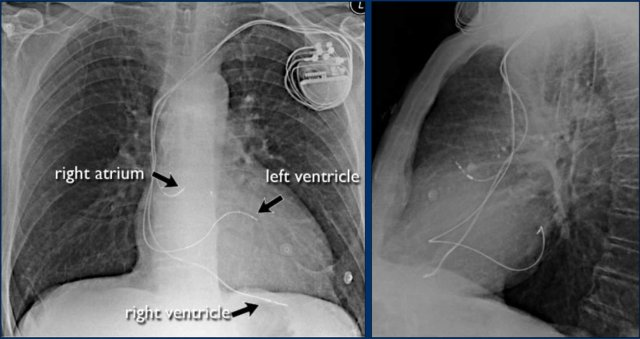

Cardiac Pacemakers

There are various types of cardiac pacing devices, each with specific lead configurations.

In this example:

- Right atrial lead

- Right ventricular lead

- Left ventricular lead via the coronary sinus (used in cardiac resynchronization therapy)

Indication for cardiac resynchronization therapy:

- Patients with ventricular dyssynchrony benefit from biventricular pacing, which improves ventricular coordination and enhances cardiac output.